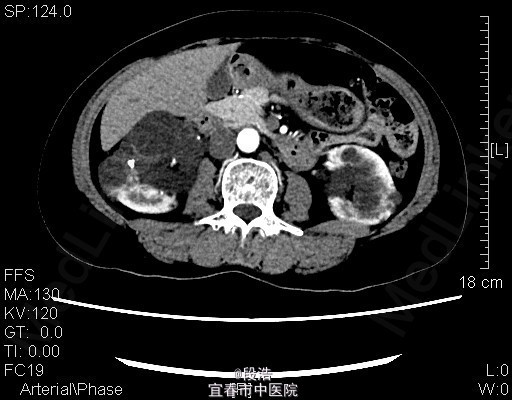

1、中年女性,体检发现双侧肾囊肿2年 2、患者于2年余前至当地医院体检发现双侧肾囊肿,当时诉腰部稍酸胀,尿量稍增多,无尿频、尿急、尿痛,无排尿困难,无血尿、脓尿等。起病以来,患者一般情况尚可,体重无下降

3、查体:未见明显异常 4、辅助检查:2013-4-11我院中腹部CT结果考虑多囊肝(未给出图像),双侧多囊肾,双肾囊壁部分钙化;双肾多发结石。2015年5月复查结果同前。

5、诊断:多囊肝,双侧多囊肾,双肾多发结石 6、入院后完善相关检查,生化,心电图,胸片未见异常,复查ct提示多囊肝,双侧多囊肾,双肾囊壁部分钙化;双肾多发结石,排除手术禁忌症后,行腹腔镜下左肾囊肿去顶术,术后予“注射用头孢美唑钠(先锋美他醇)”抗感染、抑酸、静脉营养补液等处理,术后恢复良好,顺利出院。术后半年复查再决定另一侧的处理方式。